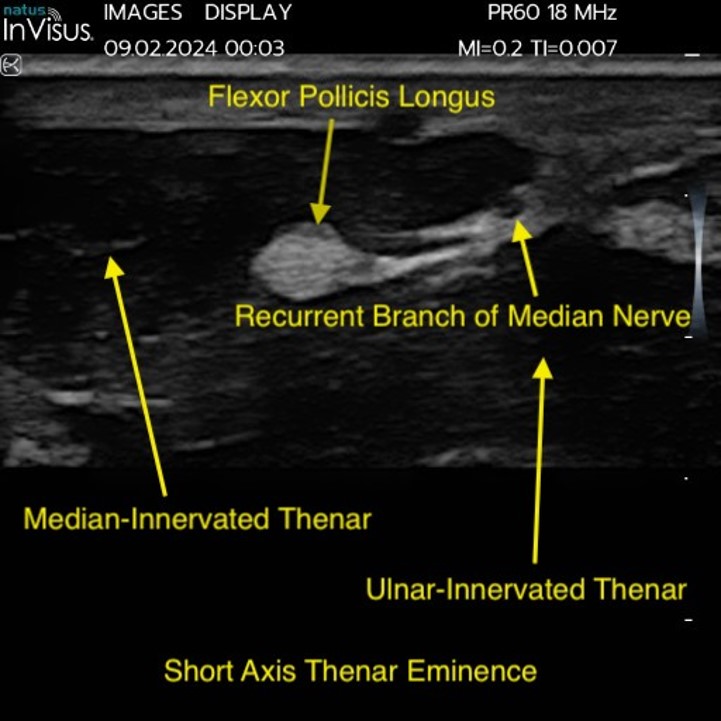

Natus InVisus Pro scan – Flexor Pollicis Short Axis